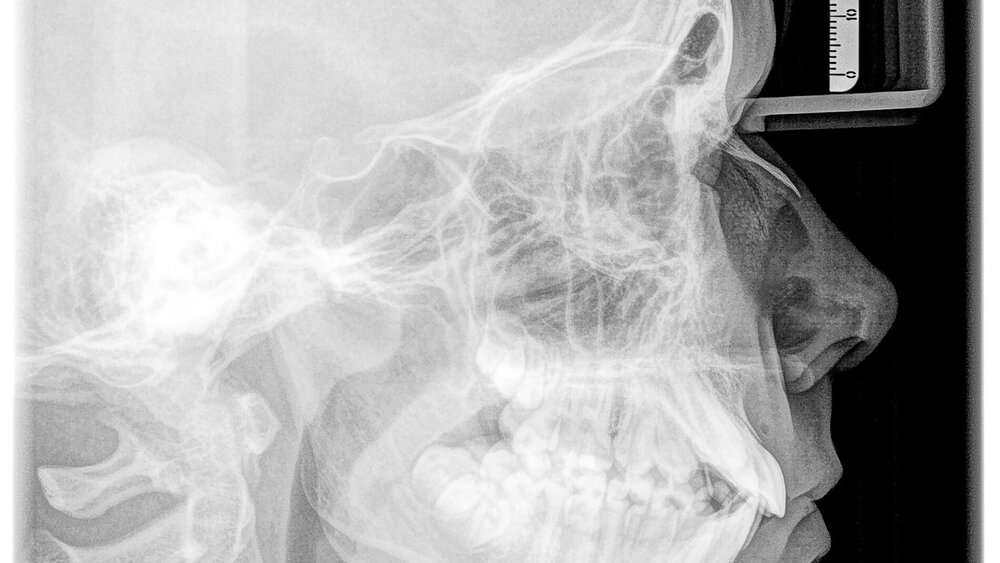

Forschende der Uni Göttingen haben kieferorthopädische Röntgenaufnahmen im Hinblick auf das Vorkommen und die Lokalisation von Nebenbefunden in Abhängigkeit des Patientenalters untersucht. Der überwiegende Teil der Zufallsbefunde lag außerhalb des dentoalveolären Bereichs.

Für die retrospektive Studie wurden Patientinnen und Patienten der kieferorthopädischen Abteilung der Uni Göttingen zufällig ausgewählt, wenn von ihnen sowohl ein OPG als auch ein FRS vorlag. Insgesamt wurden 600 Orthopantomogramm- (OPG) und Fernröntgenseiten-Aufnahmen (FRS) von 150 Kindern und Jugendlichen im Alter von 7 bis 17 Jahren und von 150 Erwachsenen bis 72 Jahren ausgewertet.

Drei Untersucher befundeten die Aufnahmen unabhängig voneinander und ordneten sie neun verschiedenen Kategorien zu (Oberkiefer, Unterkiefer, Gebiss, Nasennebenhöhlen, Kiefergelenk, Schädelbasis, Orbita, Halswirbelsäule sowie Weichteile).